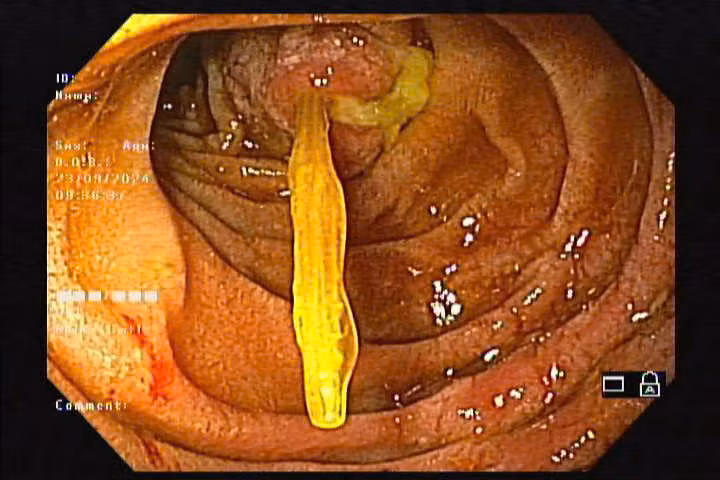

| Nội soi cho bệnh nhân nuốt phải tăm tre - Ảnh BVCC |

Qua thăm khám và chụp X-quang nghi ngờ có dị vật, các bác sĩ Khoa Nội Soi đã tiến hành nội soi thực quản – dạ dày – tá tràng bằng ống mềm và phát hiện dị vật là cây tăm tre. Một đầu tăm tre cắm vào thành D2 tá tràng gây thủng tá tràng, tạo ổ áp xe kích thước 10 – 20mm, chảy mủ trắng. Bằng dụng cụ chuyên dụng, các bác sĩ đã lấy que tăm kích thước khoảng 12cm ra ngoài, sau thủ thuật kiểm tra không chảy máu.